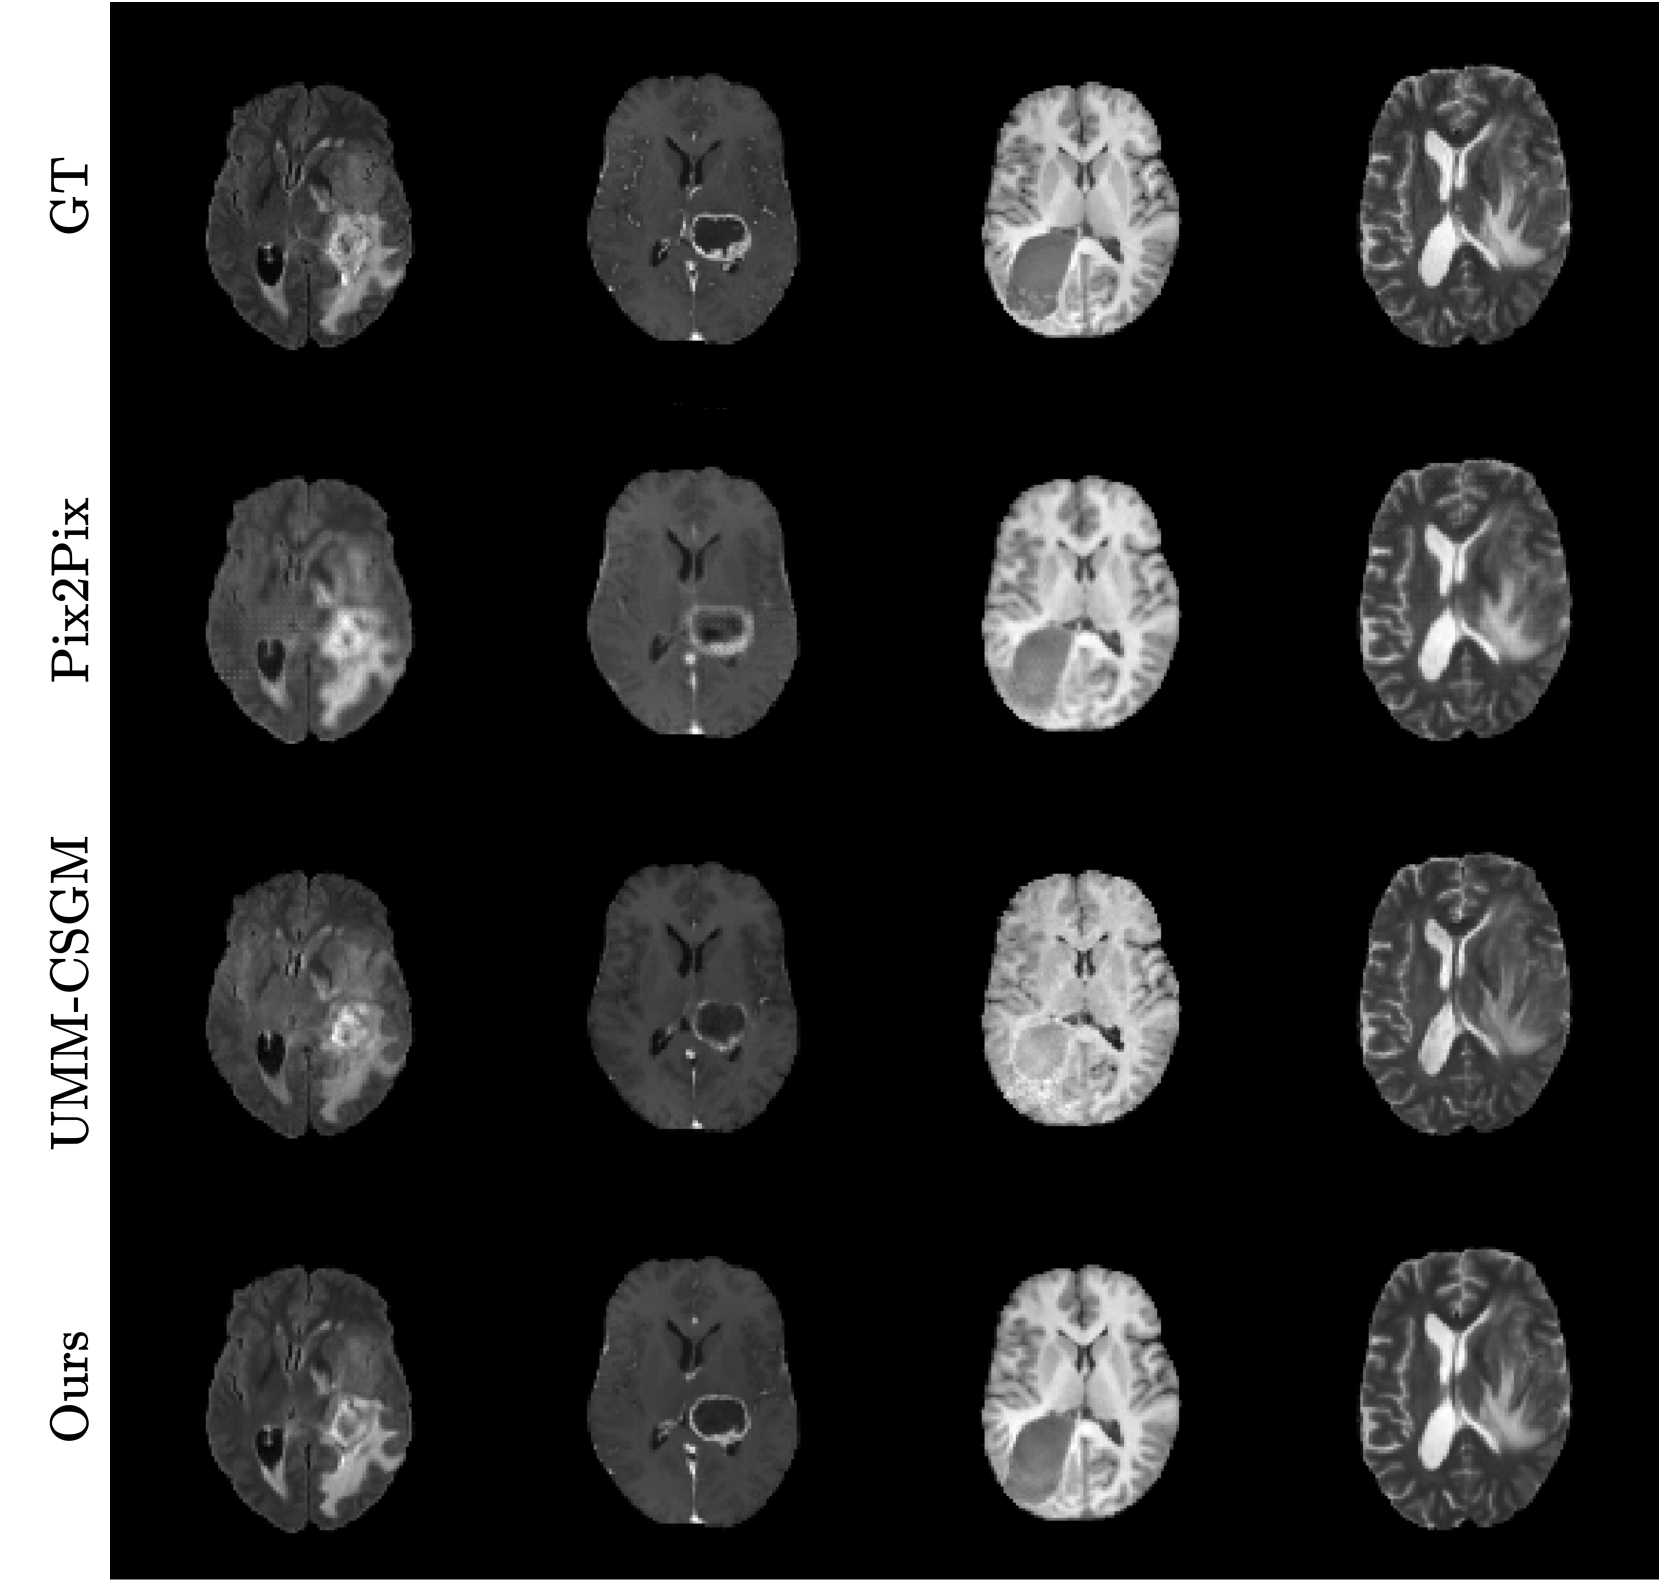

Refer to caption

Fig. 2: Comparison of translated MR sequences across different methods. Columns represent FLAIR, T1CE, T1, and T2 sequences (left to right).

Figure 2 shows qualitative comparisons of missing sequence translations generated by our method and the two other comparative methods. Our approach demonstrates more realistic and fine-grained details in the overall brain structure, with particularly precise tumor boundary representation compared to UMM-CSGM. The textural contrast between gray and white matter is also better preserved. Pix2Pix, on the other hand, exhibits missing fine-grained details and limited brain structure clarity. Each translation by our model was achieved using the same instance, underscoring its adaptability for dynamically generating missing sequences with high fidelity. In Figure 3, we present adaptive translations from various input configurations. The first row shows ground truth, while red and green borders highlight the input and synthesized sequences, respectively. A clear trend is observed: the more input sequences available, the richer the IFFN’s unified representation, particularly improving tumor delineation in T2 sequences from the second-to-last rows. However, when fewer input modalities are provided, there is a tendency for random interpolation of tumor regions, especially without key modality pairs like FLAIR/T2 or T1/T1CE. This is visible in the second row’s T1CE, which improves as more input sequences are added. Despite fewer inputs, our method reliably captures enough information to translate missing sequences, illustrating the robustness of the IFFN. Additionally, our approach, treating 3D images as a sequence of 2D slices, can easily extend to 3D image translation by processing each slice and reconstructing the full 3D volume.